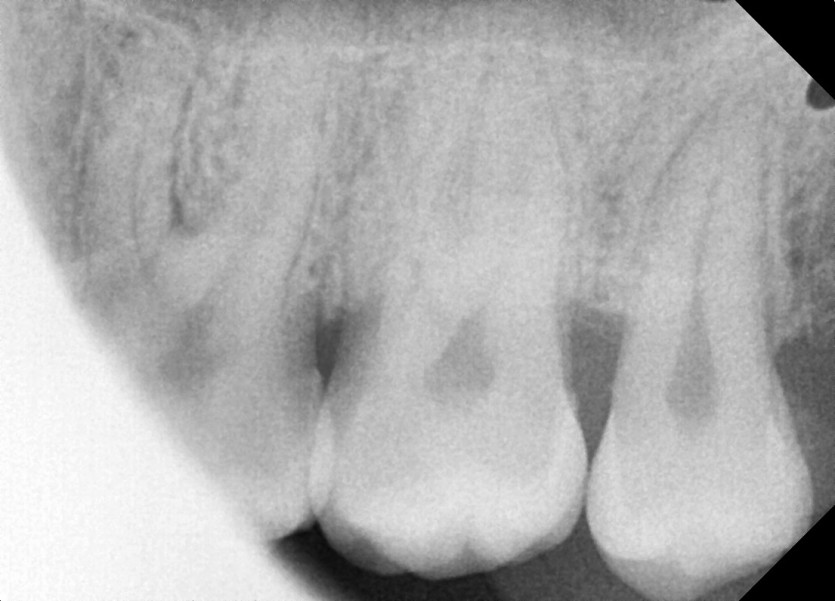

#28,38 사랑니 발치

구강 외과 전문의가 당일 발치했습니다.